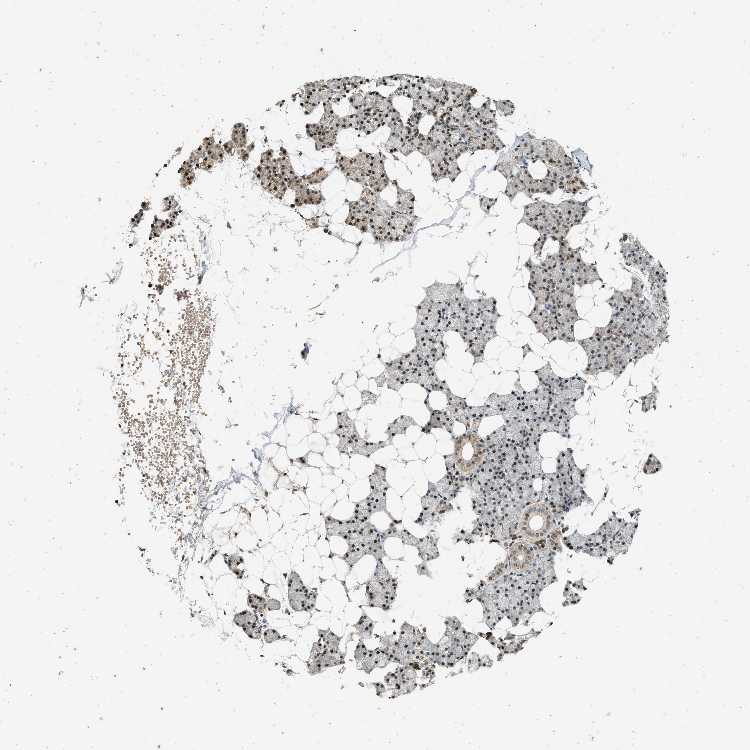

Antibody CAB018724

Glandular cells Medium